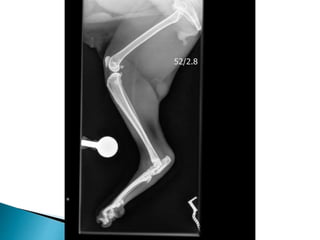

 Radiographs ***

 Radiographs

 Viral Testing- negative  Joint Culture  Cytology  Radiographs ***  Ultrasound Abdomen

• #10 He had smooth recovery from anaesthesia and seemed much more comfortable on his methadone. Cytology and Culture both were negative. Hocks and elbows to have increased WBC, predominately neutrophilic inflammation (91- 94%). Mild toxic change to the neutrophils. The right and left stifle: Low Neutrophils (< 1 x10e9/l). The majority of cells present were large mononuclear cells (85 - 87%). Immune mediated hypersensitivity type III reaction. Run through the types… I = hay fever idea – IgE released. II = IMHA like whereby antibody binds to cell surface antigen III = Antibody binds to cell suface antogen however these are solvent in blood and not attached to cells and so can settle out in various locations throughout the body. Periosteal proliferative polyarthritis occurs most often in male cats (intact and castrated), but female cats can also be affected. Cats of any age can develop this polyarthritis, but it is most common in young adults. Affected cats experience fever, lethargy, a stiff gait, and joint pain and swelling, particularly of the carpus and hock. There is sometimes concurrent edema of the skin and soft tissues overlying the joints. Lymph node hyperplasia may cause severe regional lymphadenopathy. Synovial fluid analysis reveals a moderate-to-severe neutrophilic pleocytosis and culture is negative. Papers form the 1980’s actually found that 100% of cats with chronic progressive arthritis showed FSFV or antibodies to it. But is it just incidental because this virus in particular is found in normal cats also. It has been suggested that infection with FeLV or FIV-induced immunosuppression allows FeSFV to multiply in the joints of predisposed individuals. However in papers that I came across, surprisingly there isn't an increased incidence of FeLV or FIV in affected cats. It occurs more commonly in young, entire or castrated, male cats less than 5 years of age. Radiographic changes may not be evident for the first 10–12 weeks of illness and then early findings include periarticular soft tissue swelling and mild periosteal proliferation. This matache Koshka to a T being that after roughly two months of steroid effectiveness. An abnormally coarse trabecular pattern of the bones of affected joints. Over time, the periosteal proliferation worsens and extends beyond the confines of the joint, which may lead to ankylosis. Periarticular osteophytes, subchondral cyst-like lesions and periarticular erosions are evident. Calcification and erosion of bone may occur at the attachment of ligaments and tendons, causing painful lesions (enthesopathies).